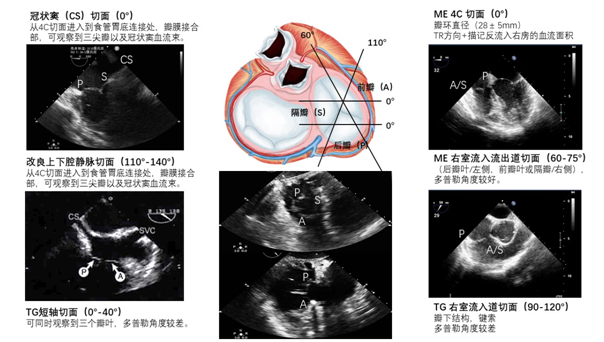

1996TEE20个切面发表以来,切面标准化最大的进展是目标导向和问题导向切面的提出。2014年,本专家共识提出了适用于麻醉急诊和术中循环监测的TEE-FOCUS四个基本切面,临床证明适用于术中循环监测,针对心脏大血管外科手术增加升主动脉长轴切面,降主动脉短轴切面,对体外循环手术主动脉插管的安全性监测,了解主动脉插管部位有无粥样班块及斑块的分级。

截至目前,TEE-FOCUS包括6个基本切面(图5-6),其中有4个关于心脏的基本切面和2个关于大血管的基本切面:1. 左心室长轴切面,2. 右心室流入流出道切面,3. 降主动脉短轴切面,4. 经胃底心室短轴切面,5.食管中段四腔心切面,6.升主动脉长轴切面(新增)。TEE-FOCUS中的6个基本切面具体评估要点如表2所示。对于非心脏手术TEE-FOCUS也包括6个基本切面,不同之处是将升主动脉长轴切面替换为食管中段双腔静脉切面。